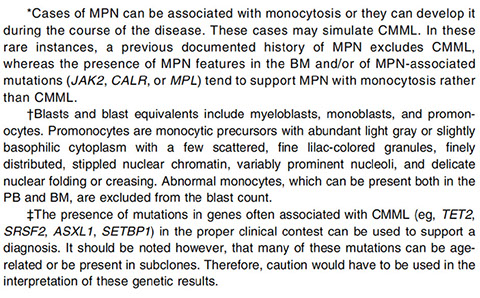

`

Clonal hematopoietic stem cell disorders

- MDS as well as MPN features

- Leukocytosis, may exceed 100x109/L

- Persistent monocytosis >1x109/L in PB

- Frequent monocytosis in BM

- <20% blasts + promonos in PB and BM

- Dysplasia in one or more cell lines (usually in the granulocytic lineage)

- MDS/MPN in which the main diagnostic feature is peripheral blood monocytosis

• Some cases follow MDS

• Some cases are therapy-related

• Mast cell aggregates (SM) may be seen

Presents as B symptoms appearing as an MPN with leukocytosis and S-megaly

- hallmark is monocytosis in PB (bm often is not really too involved) [8]

80% have Mgkc abnormalities; 30% have fibrosis and 20% have plasmacytoid monocyte nodules on BM

Diagnostic criteria (see table for all 2016 criteria):

CMML-0 has <2% blasts in PB; <5% blsts in BM

CMML-1 has 2-4% blasts PB, 5-9% blasts in BM

CMML-2 has 5-19% blasts in PB, 10-19% blasts BM or if Auer rods are present

JAK2 V617F mutation common (vs other BCR-ABL1 negative MPNs)

Mild eosinophilia may be present, which can mimic PDGFRA/B neoplasms

DDx

Reactive monocytoses: malignancy, infection, inflammation, recovering BM post-chemo, G-CSF tx, TB brucellosis, leishmaniasis, endocarditis

Neoplastic: CML, AML, MDS with monocytic progression, MPN with monocytic progression, JMML

Diagnostic pitfalls

• Monocytosis as a component of a reactive phenomenon – infection, inflammatory conditions such as collagen vascular disease, chronic neutropenia, splenectomy, hemolytic anemia, immune thrombocytopenic purpura

• Evolution of CMML-like features in known MPN or MDS. Do not reclassify the disease

• Monocyte morphology: Monocytes vs. abnormal monocytes vs promonocytes (a.k.a. blast equivalents)

Monocytosis in classic MPN

• Do not reclassify disease

• Sign of disease progression

• PMF with monocytosis shows higher JAK2 V617F VAF than CMML (42% vs 17%)

- Must do a BM to prove that the disease is not AML with mature circulating monocytes [7]

Px:

Average survival is 20-40 months

- AML occurs in up to 30%

Blast count is most important prognostic indicator

CMML diagnostic criteria

CMML diagnostic criteria

CMML, PB

CMML, BM

CMML, monocyte morphology, from Dr. Reichard lecture, LASOP, 1/18/2020

CMML, monocyte morphology. Monoblasts and promonocytes have fine nuclear chromatin (maybe the most important feature. Monoblasts have high N:C ratio. Promonocytes have delicate nuclear folding. [8]